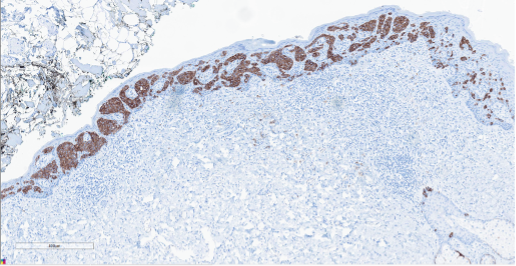

Figure 4. Immunohistochemistry. CK7, a membranous-cytoplasmic stain showing diffuse positivity in a nest-like pattern.

Figure 5. Immunohistochemistry. GATA3, a nuclear stain highlighting the tumor cells in the same nest-like pattern as CK7.

Primary Paget disease of the vulva is a rare in situ adenocarcinoma that arises in the labium minus or majus and most commonly affects postmenopausal women. Patients may present with itching or burning that has been present for years before undergoing a biopsy. On physical examination, the vulvar lesion is raised and may look erythematous or eczematous and can extend to the vagina and cervix. On microscopy, the tumor cells may be singly dispersed or arranged in a nested pattern. The nuclei are large and vesicular with prominent nucleoli. There is abundant pale, eosinophilic cytoplasm and intracytoplasmic mucin can be seen. The tumor is most commonly positive for CK7, GATA3, CEA, and GCDFP-15 and negative for PAX8, SOX10, and HPV ISH. This panel is helpful when differentiating it from other entities. However, there are reports of p16 and PAX8 positivity in Paget disease of the vulva, so careful interpretation of morphologic features and ancillary studies is important.